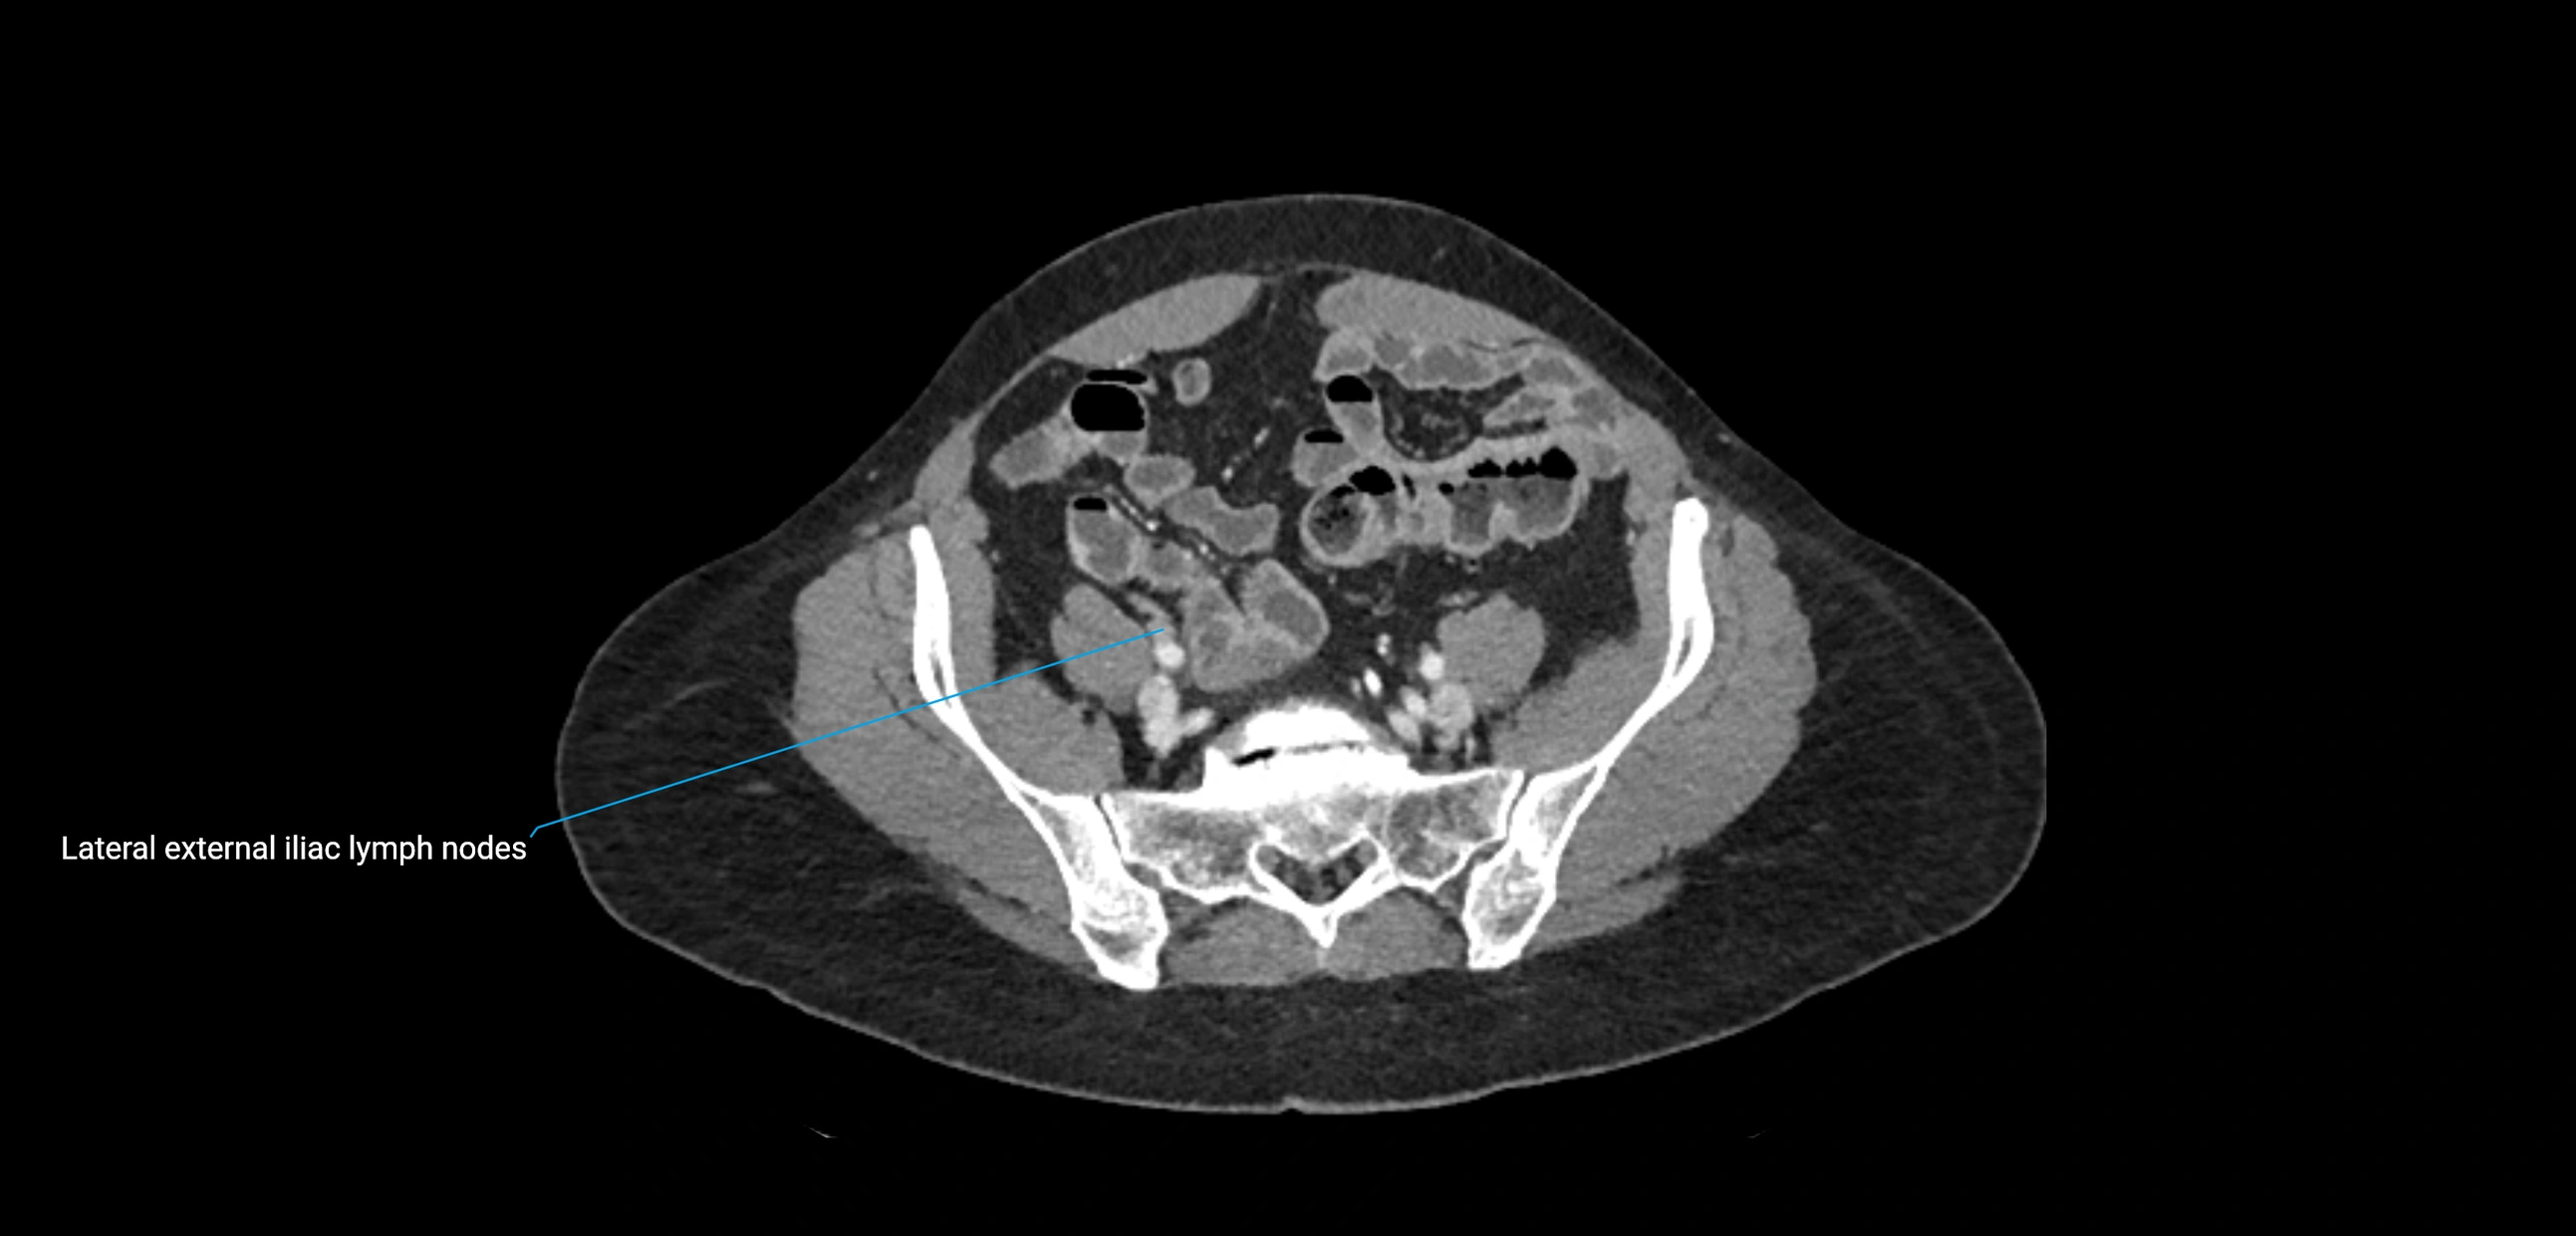

CT image

image